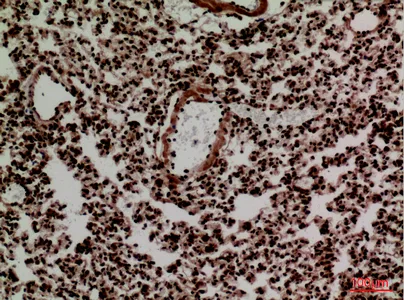

FOXP1 Rabbit Polyclonal Antibody

Cat: APRab11113